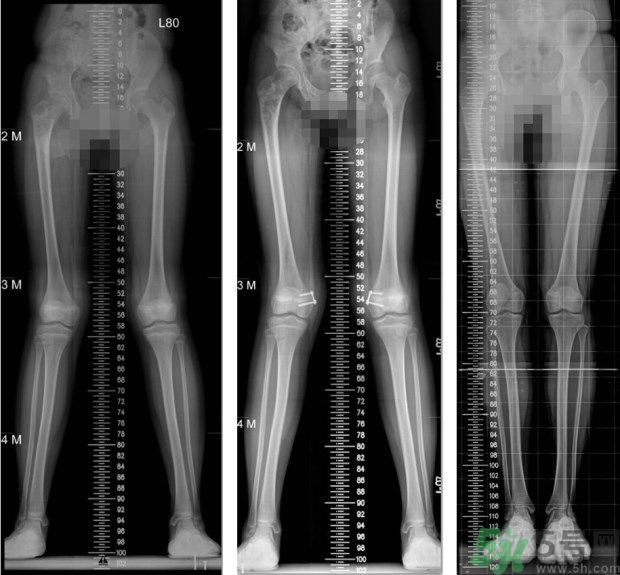

左圖:矯正前,11歲女童,大腿內(nèi)側(cè)的生長(zhǎng)板過(guò)度發(fā)育,導(dǎo)致雙腳X型腿;中圖:矯正中,在大腿內(nèi)側(cè)的生長(zhǎng)板,夾上小夾子,矯正過(guò)度發(fā)育的生長(zhǎng)板;右圖:矯正後,經(jīng)過(guò)8個(gè)月的生長(zhǎng)板導(dǎo)引,恢復(fù)筆直的雙腳。(照片提供:王廷明 醫(yī)師)